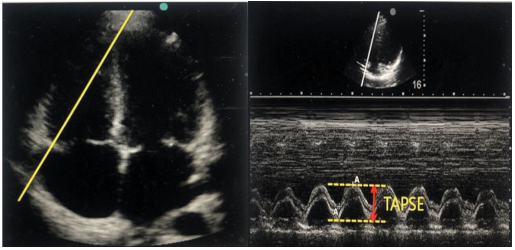

(1)三尖瓣瓣环收缩期运动(TAPSE):在心尖四腔心切面,采用M型超声心动图,取样点置于三尖瓣瓣环侧壁,测量三尖瓣瓣环侧壁运动曲线的上下两点的距离图13正常情况下,TAPES的值应该大于2.0 cm,若该值小于1.5 cm,则表明右心收缩能力的明显降低和较高的死亡率。

图片

图13. TAPES的测量示意图